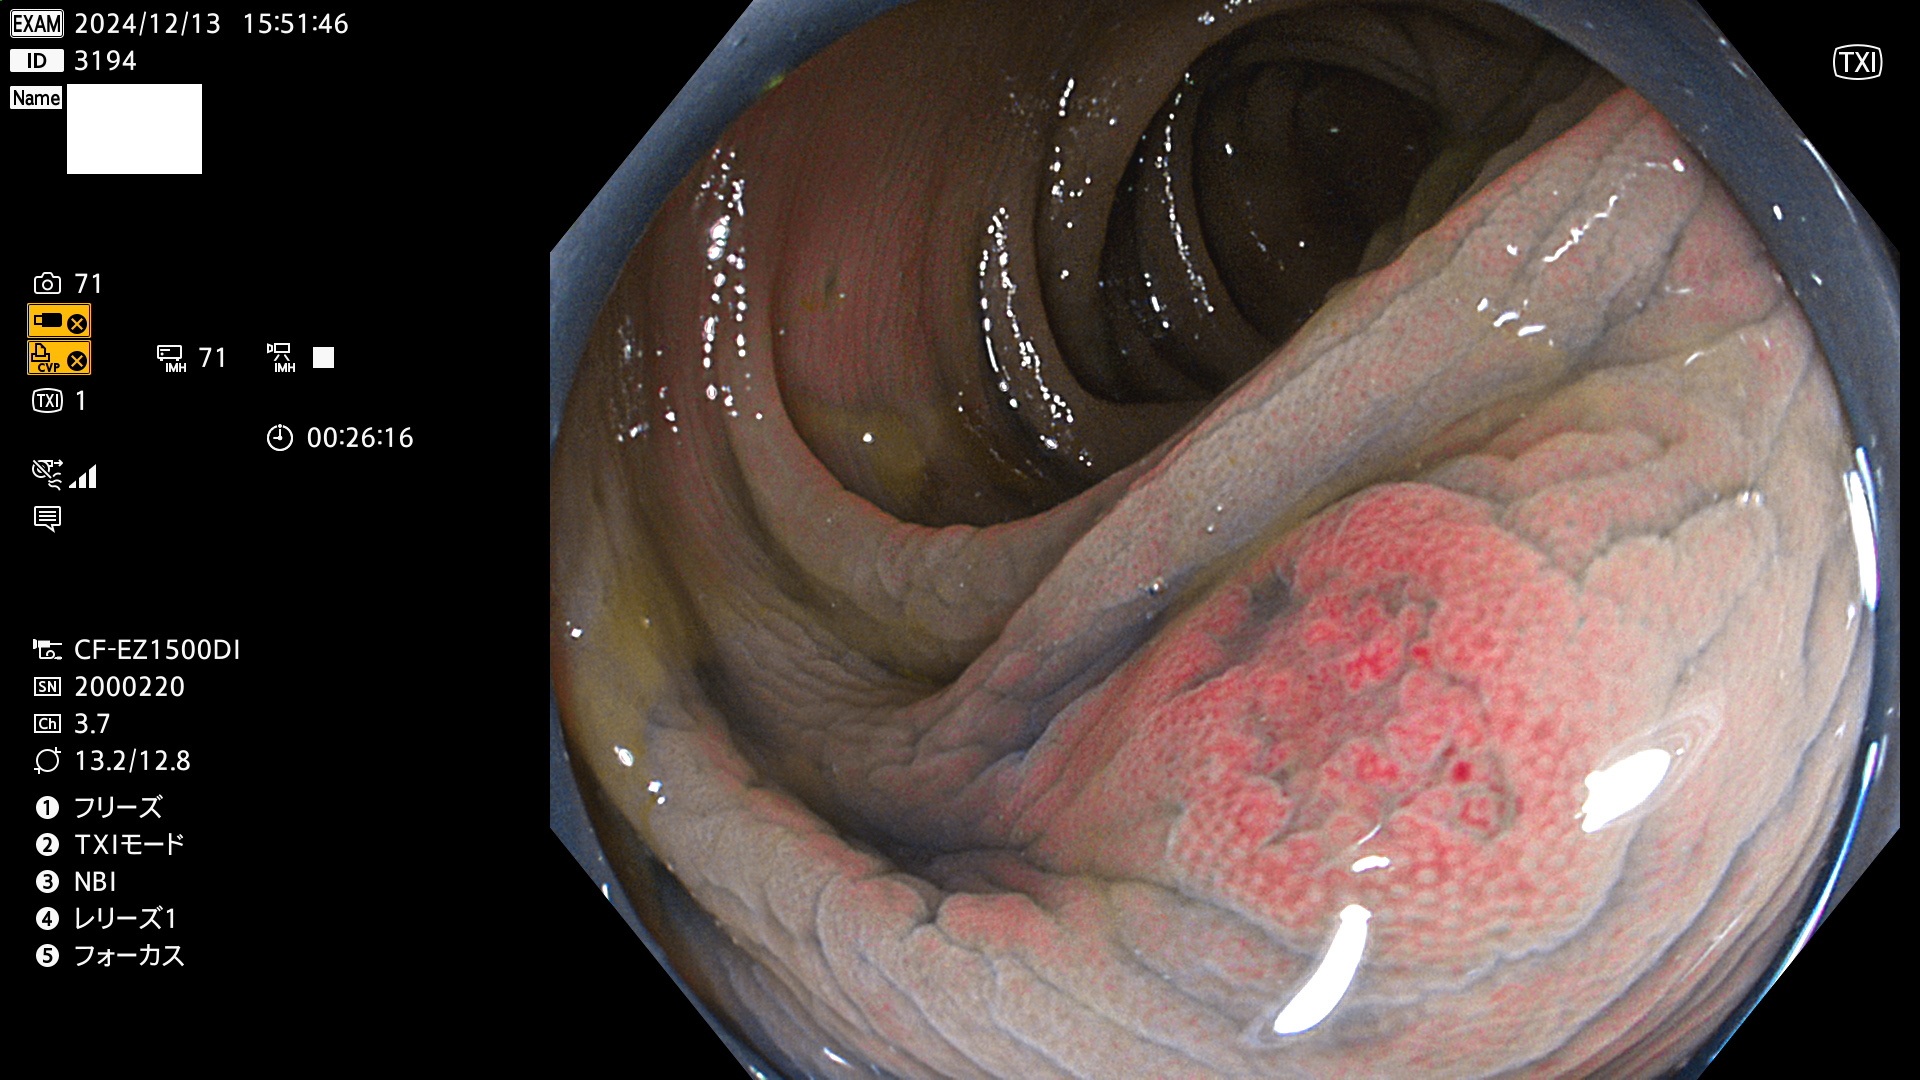

今週のUb、Uc型腺腫

完全に平坦な物をUb、陥凹している物をUcと呼びます。最も発見が難しく危険な病変です。

毎週の検査(木・金・土・日)に発見されたUb、Uc型・腺腫を、その週の日曜の夜にUPし1週間、提示します。

抽出の対象期間 2024年12月12日〜12月16日の5日間(60件の検査)13件 (13/60=21%)